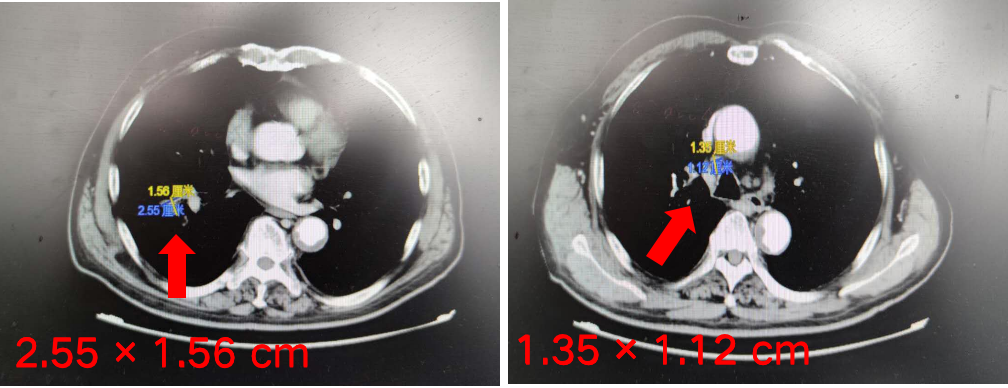

经患者充分知情同意并签署知情同意书后,予以免疫联合化疗方案“替雷利珠单抗200 mg + 白蛋白紫杉醇300 mg+卡铂300 mg,d1,q3w,ivgtt”治疗4周期,疗效达到PR。

本例患者为右肺鳞癌(T4N3M0,IIIC期),伴多发淋巴结转移。经替雷利珠单抗联合化疗治疗,2个周期后右肺病灶和多发淋巴结转移病灶直径均明显缩小,疗效评价达到PR。患者目前已联合用药4周期,疗效持续PR,PFS已超4个月,病情平稳,安全性良好。